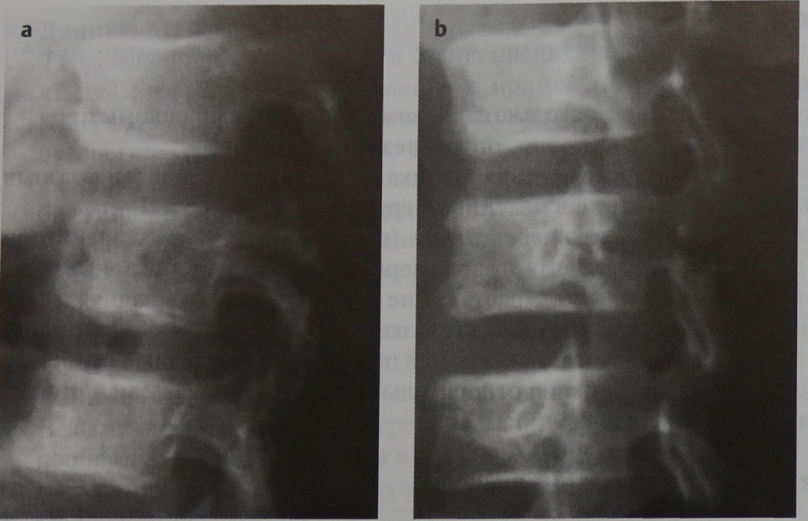

Атрофией считается уменьшение передне-заднего измерения спинного мозга меньше 7 мм в шейном отделе и меньше 6 мм в грудном. Участок атрофии может быть локальным или протяжённым, если он распространяется более чем на 2 позвонковых сегмента. При МРТ позвоночника видно, что граница атрофии спинного мозга нечёткая. Распространённая атрофия является типичным отдалённым последствием спинальной травмы.

Хроническая травма. Компрессия спинного мозга. Атрофия. Сагиттальная Т2-зависимая МРТ грудного отдела позвоночника.